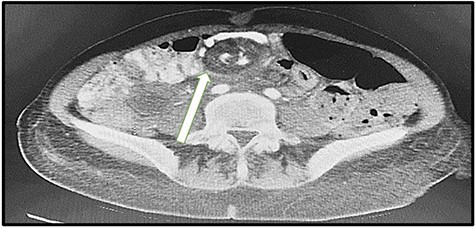

A 48-year-old-lady presented to our emergency department with 3 days history of colicky abdominal pain. The patient had a background history of LRYGB that was done 2 years ago and a history of laparoscopic internal hernia repair that was done in November 2020. On examination, she was vitally stable (P: 88, BP: 120/86, T: 37.0), with an abdominal examination of mild tenderness at the left upper quadrant region. Her initial laboratory investigations were WBC: 9.6 109g/l, HB: 9.0, PLT: 275, kidney function test (creatinine: 72, urea: 4.5) and lactic acid was normal: 0.8 (range: 0.5–2.2). CT scans of abdomen and pelvis showed mesenteric vessels swirl and dilated small bowel loops with the transitional zone at the jejunal anastomosis (Fig. 5). The patient was improving with intravenous fluids; thus, the initial decision was to conserve. However, 2 days later, symptoms increased. Repeat CBC and lactic showed a marked increase in WBC and lactic acid (12.8 109g/l, 7.8), respectively. Therefore, the patient was shifted to the operating room.